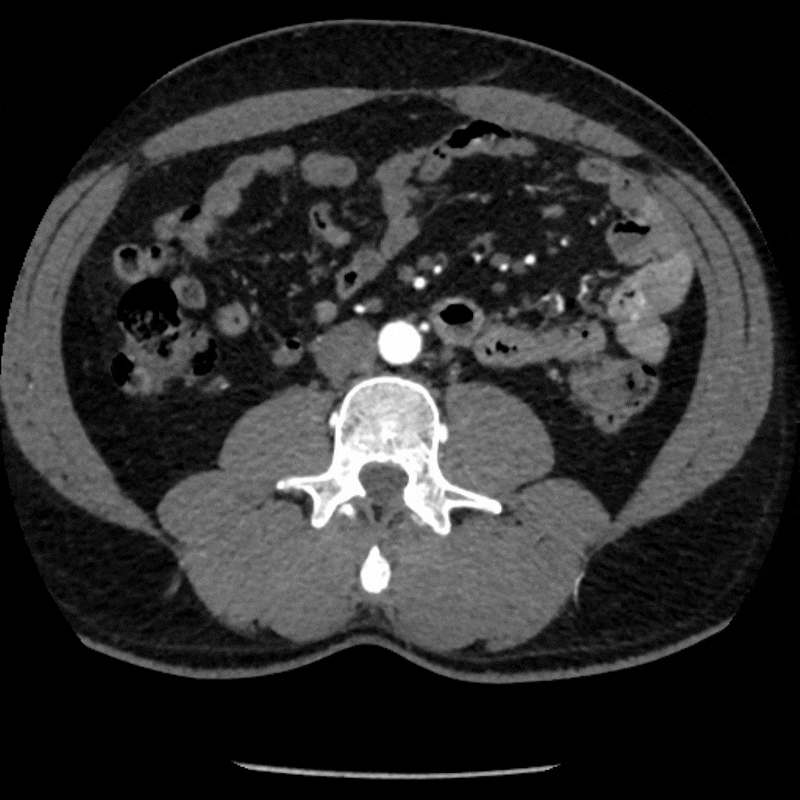

Figure B: Axial CT of the pelvis in a relaxed position.

Figure C: Axial CT in a stressed position.